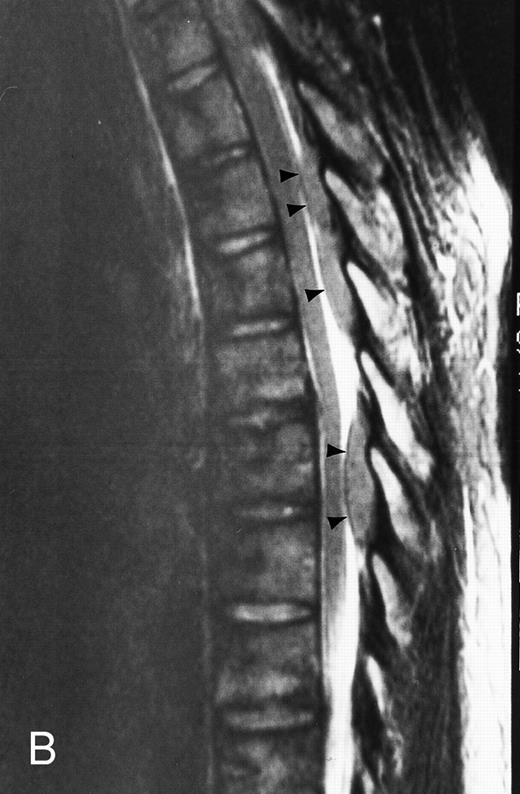

Diffuse MR pattern of abnormal marrow in a 29-year-old man with AML: T1-weighted sagittal (500/10, TR/TE) (A), T2-weighted, fat-suppressed fast spin echo sagittal (5000/96, TR/TE, ET 16) (B), and enhanced T1-weighted sagittal (500/10, TR/TE) (C) MR images of the thoracic spine. The abnormal vertebral bodies in (A) are dark and isointense to the intervertebral discs and in (B) they become bright. In (C), the abnormal marrow enhances and the vertebrae become brighter than the discs. Note extraosseous mass (arrowheads) in the posterior epidural space with preservation of the bony cortex.